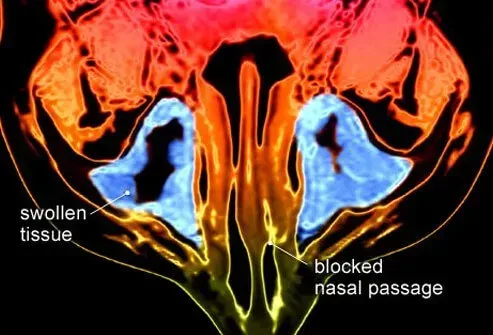

L'inflammation des tissus qui remonte les sinus est appelée sinusite. Les infections avec des virus ou des bactéries ou des allergies provoquent la plupart des cas de sinusite.

Sinusite chronique

La sinusite chronique est définie comme une inflammation des sinus qui dure plus de trois mois. Il est caractérisé comme une sinusite chronique avec ou sans polypose. La sinusite chronique peut être causée par des allergies anatomie anormale des sinus qui entraîne un blocage chronique (polypes) ou des problèmes dentaires.